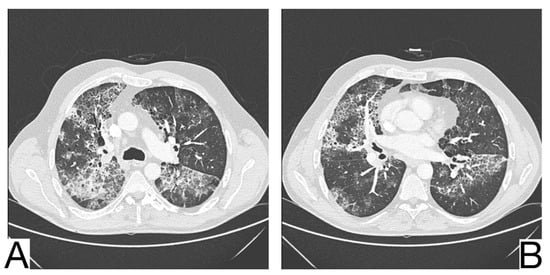

1. Early phase/Stage 1—days 0–4. Ground glass opacities represent the main radiological characteristic [] (Figure 4A);

Figure 4. Imagistic findings in COVID-19 (A). Multiple areas of ground glass infiltration (patient on the third day of symptoms) (B). Bilateral patches of ground glass and subsegmental consolidation (C). Ground glass and consolidation with air bronchogram (8 days after onset) (D). Diffuse ground glass infiltration (white lung appearance). Note. Adapted from Hefeda et al. (2020) [].

2. The progressive phase/Stage 2 refers to days 5–8, and the hallmark is a cobblestone appearance (Figure 4B) coexisting with extensive ground-glass opacities and condensation foci [];

3. Peak phase/Stage 3 is typical for days 9–13, and CT shows pulmonary condensations (Figure 4C), sometimes surrounded by a halo of ground glass.

4. The absorption phase/Stage 4 begins around day 14; areas of ground glass together with linear condensations are appreciable (Figure 4D).

Opacities are usually bilateral and subpleural, having an apicobasal gradient of distribution. Additional radiological features are enlargement of the peripheral pulmonary vessels, while pleural effusions, pulmonary nodules, and mediastinal lymphadenopathy are rare [].